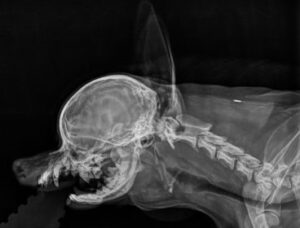

Röntgenkuvissa todettiin lähes koko matkaltaan selkeästi laskeutunut henkitorven rakenne ja erittäin ahtautunut nielun rakenne johtuen ylipitkästä ja juurestaan paksusta kielen rakenteesta, synnynnäisesti ylipitkästä etuosastaan kaareutuvasta kuonon yläosan rakenteesta, sekä suhteessa liian pienestä alaleuasta.

Hengitysteiden tähystyksessä todettiin pitkälle edennyt tracheakollapsi eli henkitorven heikkoustila, jolloin henkitorven rustorenkaat ovat painuneet kasaan ja henkitorven katto osuu vastakkain alaosan kanssa aiheuttaen vakavan ilmankulun esteen sisäänhengitettäessä.